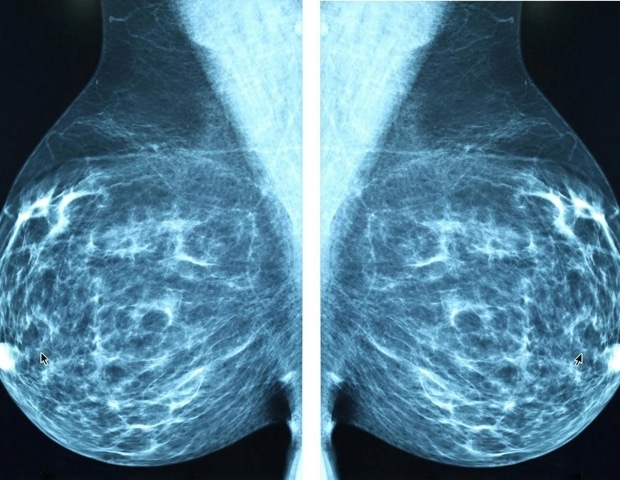

Νέο μίνι υπερηχογραφικό σύστημα για πρώιμη ανίχνευση καρκίνου του μαστού

Η έγκαιρη ανίχνευση του καρκίνου του μαστού είναι κρίσιμη για την επιτυχία της θεραπείας, και οι ερευνητές του MIT έχουν αναπτύξει ένα καινοτόμο μίνι υπερηχογραφικό σύστημα που υπόσχεται να διευκολύνει τη διαδικασία. Το νέο αυτό σύστημα, που μπορεί να χρησιμοποιηθεί είτε στο σπίτι είτε σε ιατρείο, στοχεύει στην αύξηση της συχνότητας των εξετάσεων για άτομα που διατρέχουν υψηλό κίνδυνο ανάπτυξης καρκίνου του μαστού.

Ενώ οι περισσότερες περιπτώσεις καρκίνου του μαστού ανιχνεύονται μέσω τακτικών μαστογραφιών, υπάρχει πάντα ο κίνδυνος ανάπτυξης όγκων μεταξύ των ετήσιων εξετάσεων. Αυτοί οι όγκοι, γνωστοί ως «καρκίνοι διαστήματος», αντιπροσωπεύουν το 20-30% όλων των περιπτώσεων καρκίνου του μαστού και είναι συχνά πιο επιθετικοί. Η αύξηση της συχνότητας των υπερηχογραφικών εξετάσεων, παράλληλα με τις μαστογραφίες, μπορεί να συμβάλει στην έγκαιρη ανίχνευση αυτών των όγκων.